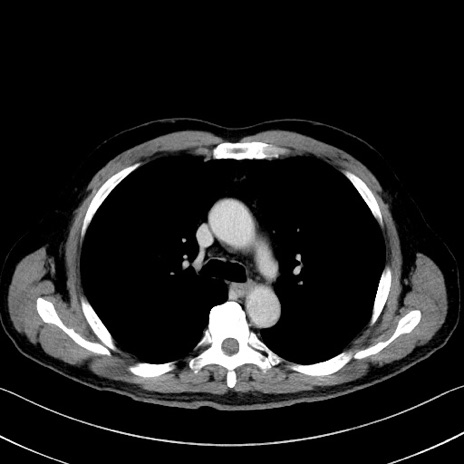

症例35(横断像)

【症例】70歳代 男性

【主訴】腹部膨満、嘔吐

【現病歴】昨日より腹部膨満感出現。本日増悪し、仙痛出現。嘔吐あり、受診。

【既往歴】糖尿病、胆摘後

【身体所見】BP 149/80mmHg、HR 74/min、BT 35.9℃、腹部:膨満、軟、圧痛なし。腸雑音減弱あり。上腹部正中切開瘢痕あり。

【データ】WBC 13500、CRP 1.72